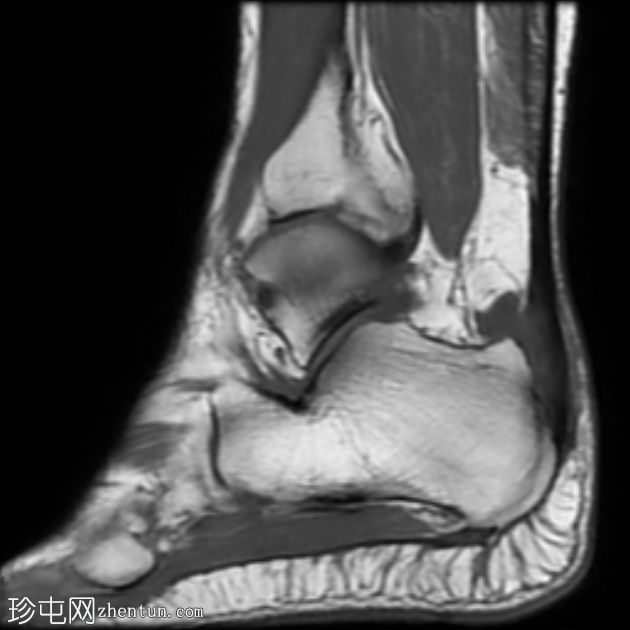

MRI

矢状位

T1

跟腱插入

,伴有跟腱明显增厚,可诱发异常信号、跟腱后滑囊炎、跟骨后突及骨髓水肿信号。

Haglund综合征的检查结果令人印象深刻。

Haglund综合征是指以下三联征(Haglund三联征):

跟腱插入性病

跟腱后滑囊炎

Haglund畸形(即跟骨后上外生骨疣)